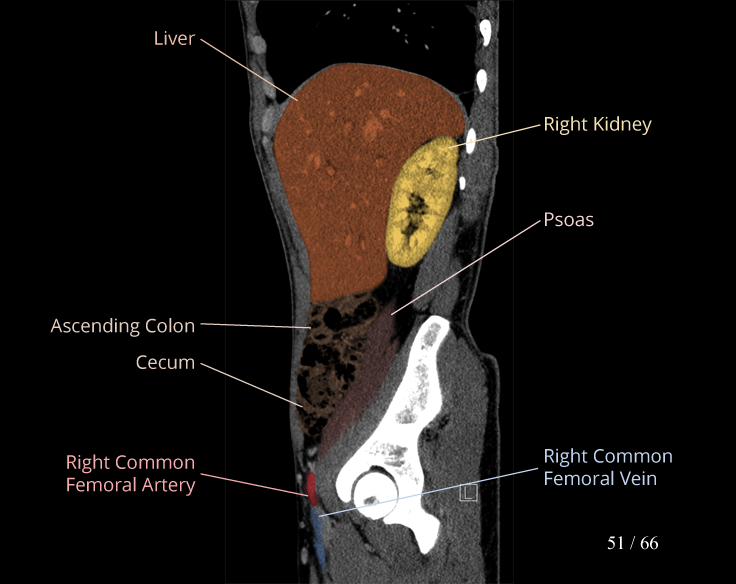

Body

Covers abdominal CT anatomy.